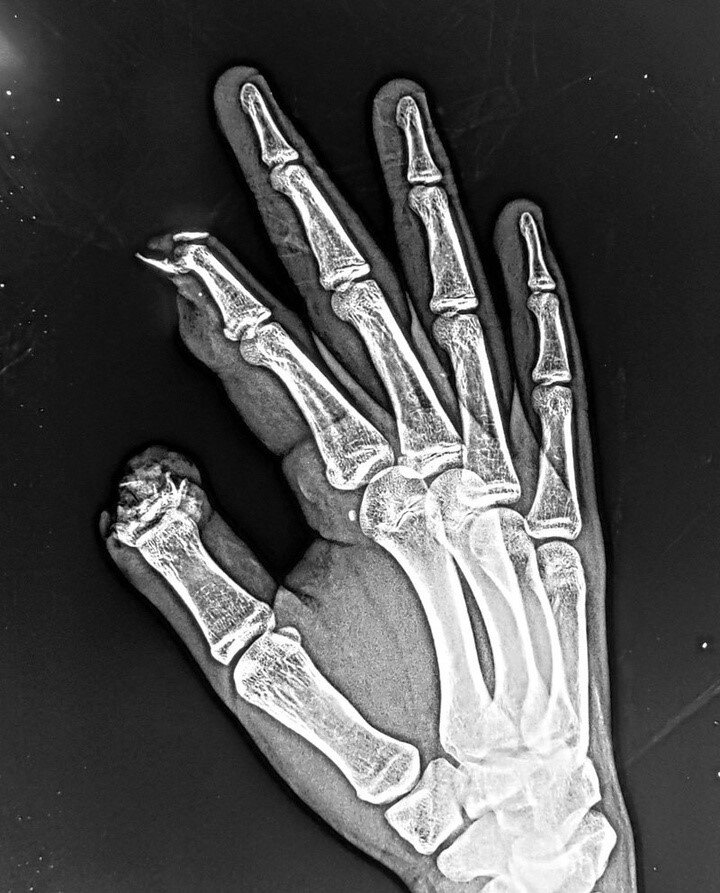

На фото - результат взрыва петарды в руке 15 летнего подростка в новогоднюю ночь. По итогу - мальчик лишился двух фаланг на правой руке.

Трагическое происшествие, связанное с пиротехнической новогодней атрибутикой, произошло в Химках на улице Некрасова 1 января около часа ночи. В руках у 15-летнего мальчика взорвалась петарда. Взрывом подростку оторвало два пальца на правой руке. Свидетели происшествия вызвали скорую помощь. Мальчика госпитализировали в одну из московских клиник.